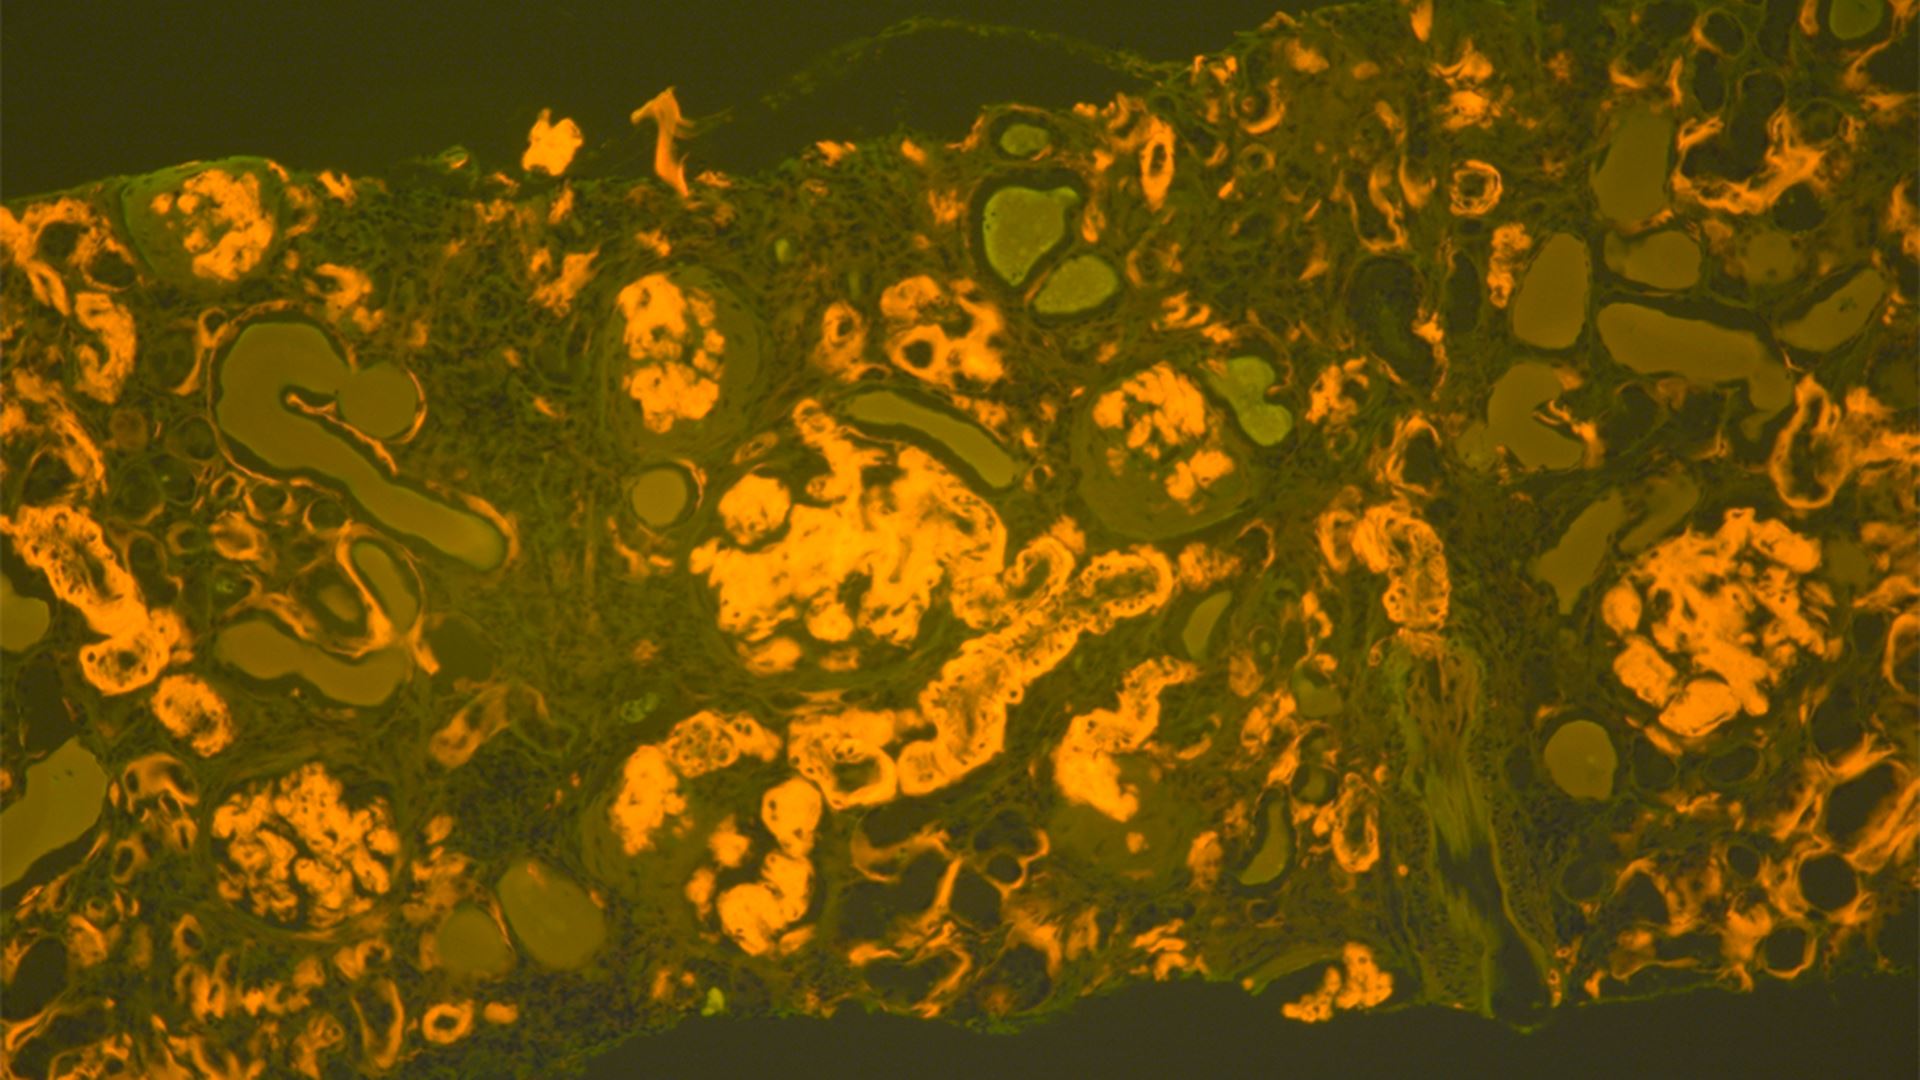

Amyloidosis is a rare but serious disease caused by the buildup of abnormal amyloid deposits in the body. The new guideline aims to support earlier and more accurate diagnosis, which is critical for effective treatment but has often been challenging for laboratories and pathologists.

A multi-disciplinary panel of experts reviewed more than 4,000 studies to develop recommendations on the most accurate methods for detecting amyloid, identifying fibril protein type, and evaluating sample types. The guideline provides pathologists with clear direction on appropriate testing and subtyping of amyloid-positive specimens.

• Congo Red Stain: Remains the standard for amyloid detection; other stains should be validated.